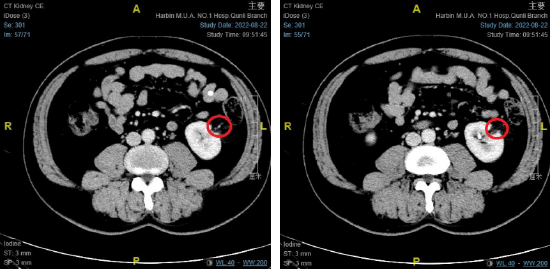

肾脏增强ct提示左肾错构瘤,红色标记处为错构瘤